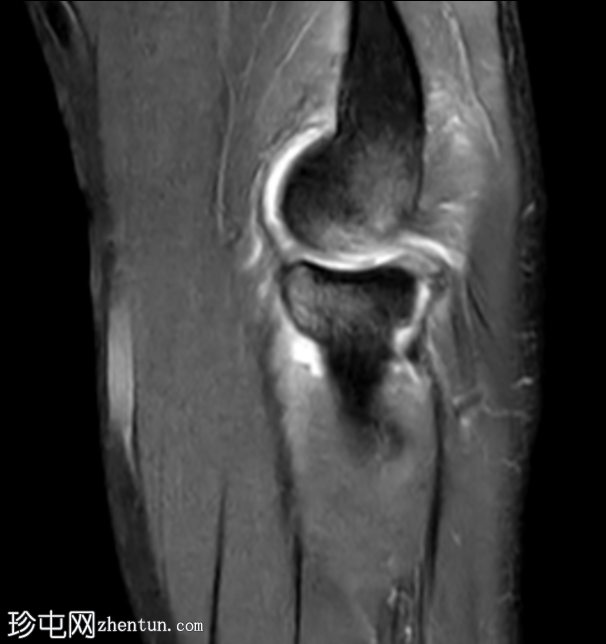

矢状位

T2加权像

肘关节外侧及后外侧结构存在复杂的损伤模式。

桡骨头及桡骨颈可见骨髓水肿,前内侧关节内部分可见低信号骨折线,符合桡骨头无移位骨折。

肱骨远端外侧髁/肱骨小头也可见明显的骨髓水肿。伴有皮质不规则、凹陷及正常轮廓消失,提示骨小梁嵌顿。

位于水肿骨内的这处骨损伤(奥斯本-科特里尔损伤)代表的是真正的撞击性骨折,而非常见的正常解剖假性缺损。

尺侧副韧带显示高度撕裂,表现为模糊的异常形态,并伴有高PD信号强度。

内侧副韧带前束近端附着点显示高PD和STIR信号以及纤维断裂,符合部分撕裂的特征。

桡骨近端周围存在广泛的软组织水肿和液体信号,提示环状韧带损伤。

旋后肌显示明显的水肿,且肱二头肌腱附着处信号异常。

另可见大量关节积液。

这是一个典型的肘关节后外侧旋转不稳病例,与既往肘关节脱位相符。

肘关节后外侧旋转不稳(PLRI)是慢性肘关节不稳最常见的类型,表现为桡骨和尺骨向后外侧方向半脱位,远离肱骨。

典型的创伤机制是跌倒时手臂处于旋后位,手掌伸展着地,从而产生轴向负荷、外翻力矩和外旋力。

这种“Horii环状软组织损伤”始于外侧尺侧副韧带(LUCL)的撕裂,LUCL是PLRI的主要限制结构,损伤会延伸至关节囊的后部和前部,严重时甚至会累及内侧副韧带。

在MRI上,后外侧旋转不稳的标志性特征是尺侧副韧带(LUCL)的断裂或变薄,在冠状位T2加权或质子密度脂肪抑制序列上显示最佳。其他辅助性发现包括:伸肌总腱起点处水肿或撕裂、后外侧关节囊内有液体信号提示关节囊破裂、矢状位图像上桡骨头半脱位,以及桡骨头骨折和后外侧上髁/肱骨小头凹陷性骨折(即奥斯本-科特里尔损伤)。